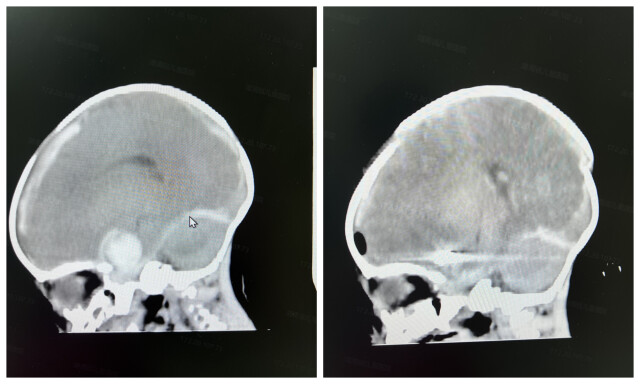

经湖南省儿童医院CT血管成像(CTA)检查,发现乐乐的左侧大脑中动脉M1段可见一巨大动脉瘤,直径约2厘米,且已破裂出血,情况十分危急。该院新生儿科、神经外科、麻醉手术科等多学科专家团队立即进行集中会诊。考虑到乐乐年龄小,血管纤细,不宜行介入治疗,开颅手术是目前唯一的治疗方法。

(术前CTA提示巨大动脉瘤)

(乐乐术前术后CT结果对比)

8月14日,出生16天的乐乐被送入手术室,刘景平带领手术团队实施手术。由于乐乐已经发生一次动脉瘤破裂,大量暗红色陈旧性血凝块覆盖乐乐整个左侧大脑表面。刘景平在显微镜下仔细清除硬膜下、蛛网膜下腔及颈动脉池内血肿后,显露出颈内动脉,乐乐的颈内动脉直径约2毫米,颈内动脉上行分叉处有一巨大动脉瘤,大小约2.1*2厘米,周围可见血凝块并与脑组织粘连。刘景平用动脉瘤探针探查仔细分离动脉瘤,切除大部分瘤体,将动脉瘤塑形后永久动脉瘤夹夹闭。手术过程中,麻醉医生时刻关注,为生命安全保驾护航。历时9小时15分钟,手术终于顺利完成。术后,乐乐被送入新生儿监护病房,在多学科医护人员的悉心照料下,乐乐克服重重难关,目前病情逐渐稳定。